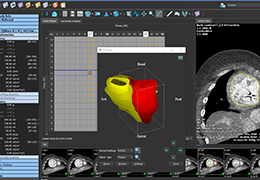

ANYTHINK 经导管主动脉瓣膜置换术分析系统